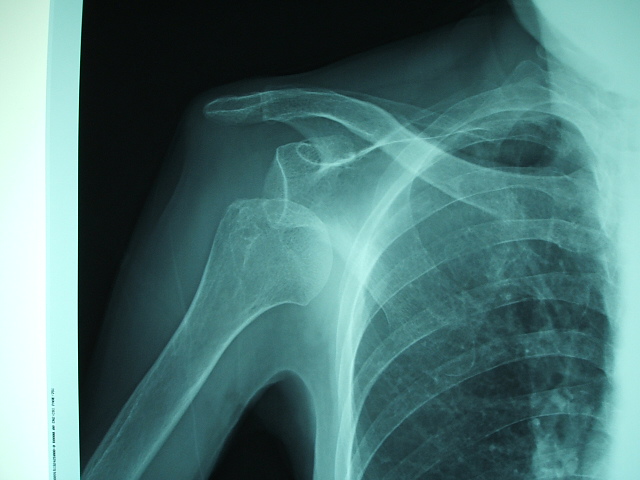

交通事故で肩が上がらなくなり、脱臼が疑われる場合は整形外科を受診しましょう。

交通事故で肩が突然上がらなくなった場合は、肩関節の脱臼が疑われます。

レントゲンを撮影して、骨折がなければ、引っ張って整復(もとの位置に戻す)します。

骨折があれば、手術が必要です。